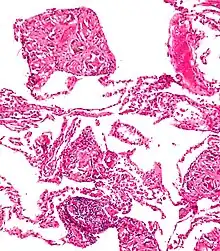

Foreign body giant cell reaction to nylon suture material

Foreign body giant cell reaction to nylon suture material.jpg.webp) Foreign body granuloma

Foreign body granuloma